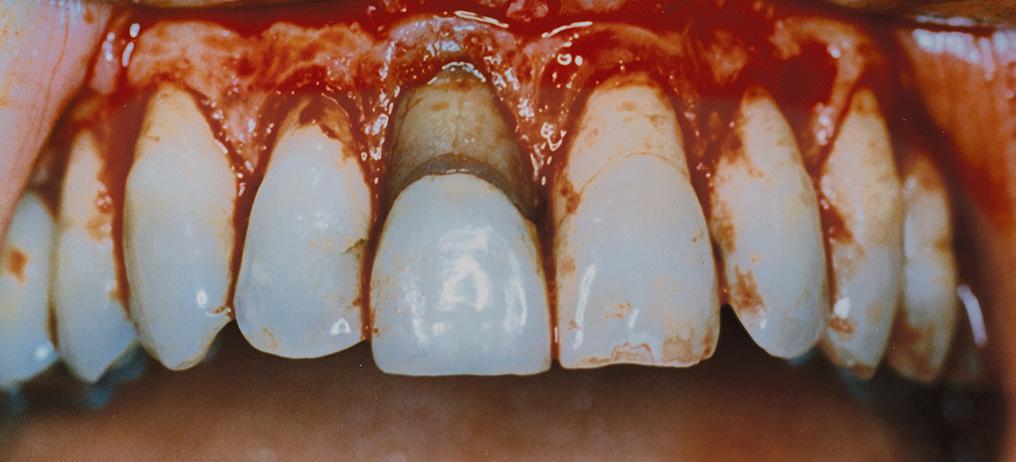

A 34-year-old patient presented with a gummy smile (Figure 8) which was classified as altered passive eruption type 1B. The patient needed a full rehabilitation of the occlusion due to a deep bite, attrition on the palatal aspects of teeth 13-23 and loss of posterior occlusal stability. The patient had excellent plaque control, no periodontal disease and a non-vital 11 due to trauma a few years prior to consultation.

Figure 8: Altered passive eruption with a component of vertical maxillary excess, showing incomplete exposure of clinical crowns.